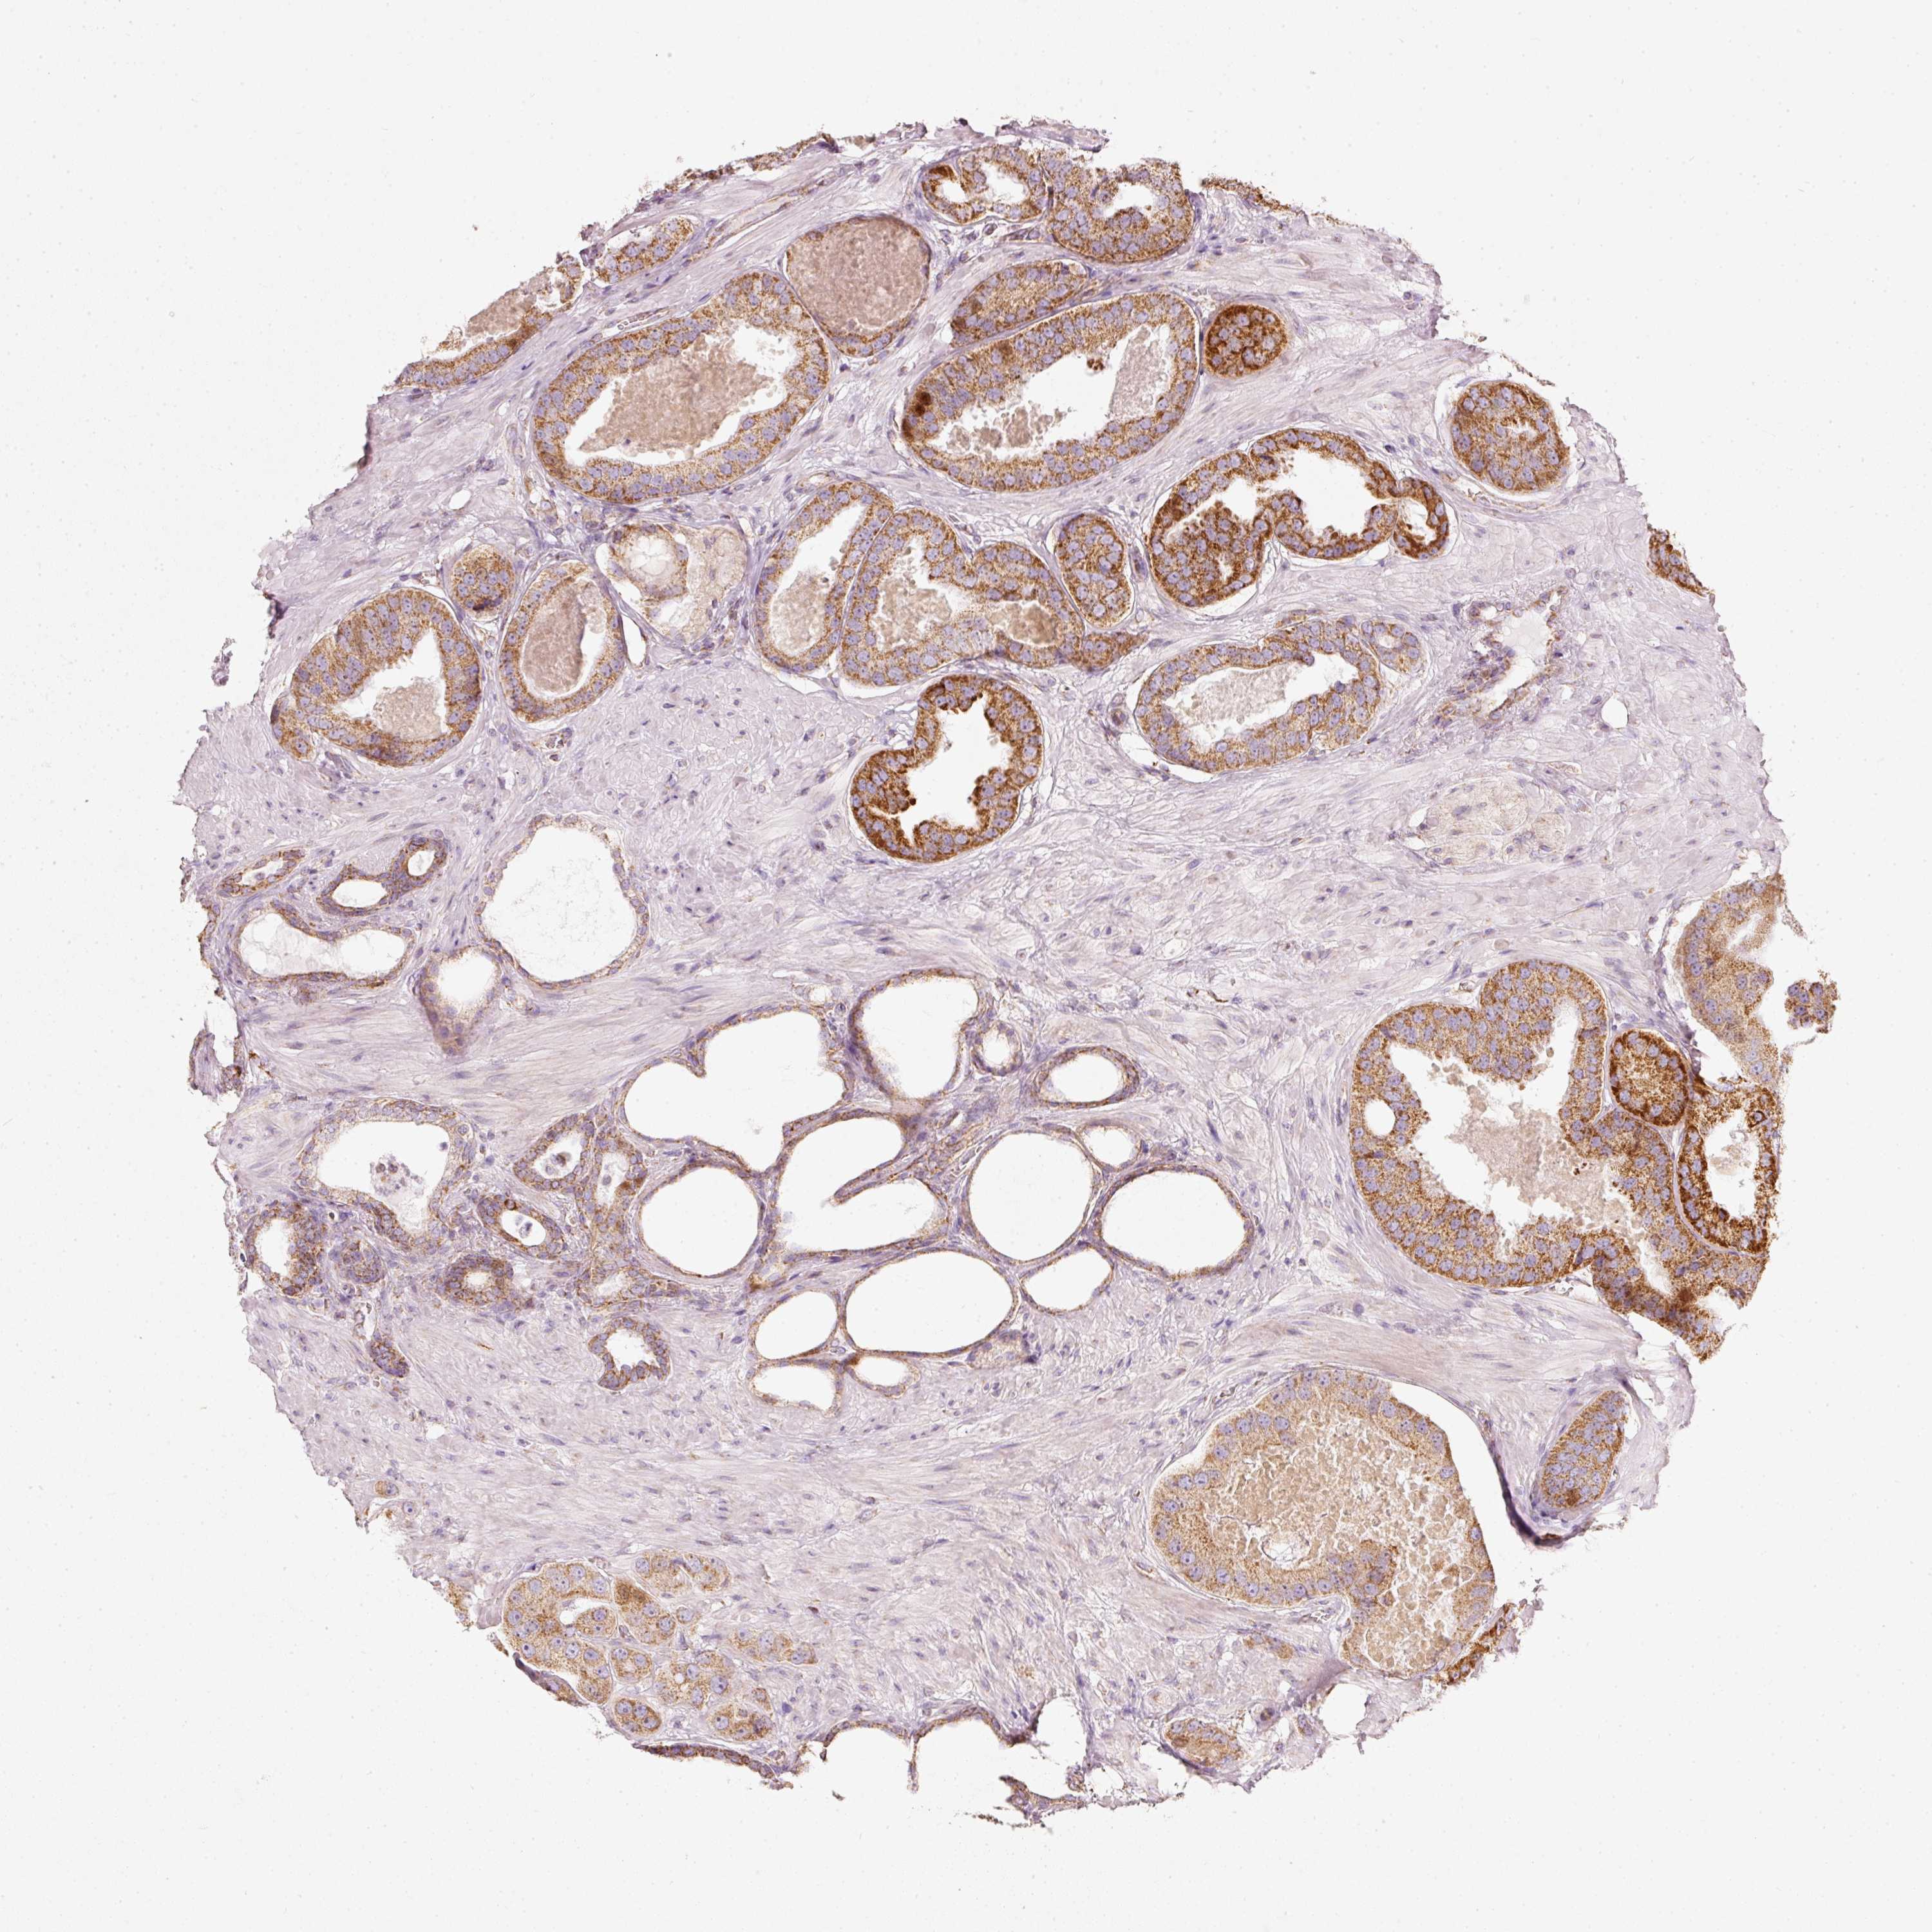

PROSTATE CANCER - Protein expressioni

A mouse-over function shows sample information and annotation data. Click on an image to view it in a full screen mode. Samples can be filtered based on level of antibody staining by selecting one or several of the following categories: high, medium, low and not detected. The assay and annotation is described here.

Note that samples used for immunohistochemistry by the Human Protein Atlas do not correspond to samples in the TCGA dataset.

Antibody stainingi

Antibody staining in the annotated cell types in the current human tissue is reported as not detected, low, medium, or high, based on conventional immunohistochemistry profiling in selected tissues. This score is based on the combination of the staining intensity and fraction of stained cells.

Each image is clickable and will lead to virtual microscopy that enables deeper exploration of all samples and also displays staining intensity scores, fraction scores and subcellular localization as well as patient and tissue information for each sample.

Antibody HPA054422

Antibody HPA060360

Staining

High

Medium

Low

Not detected

Intensity

Strong

Moderate

Weak

Negative

Quantity

>75%

75%-25%

<25%

None

Location

Nuclear

Cytoplasmic/membranous

Cytoplasmic/membranous,nuclear

Adenocarcinoma, High grade

Adenocarcinoma, Low grade